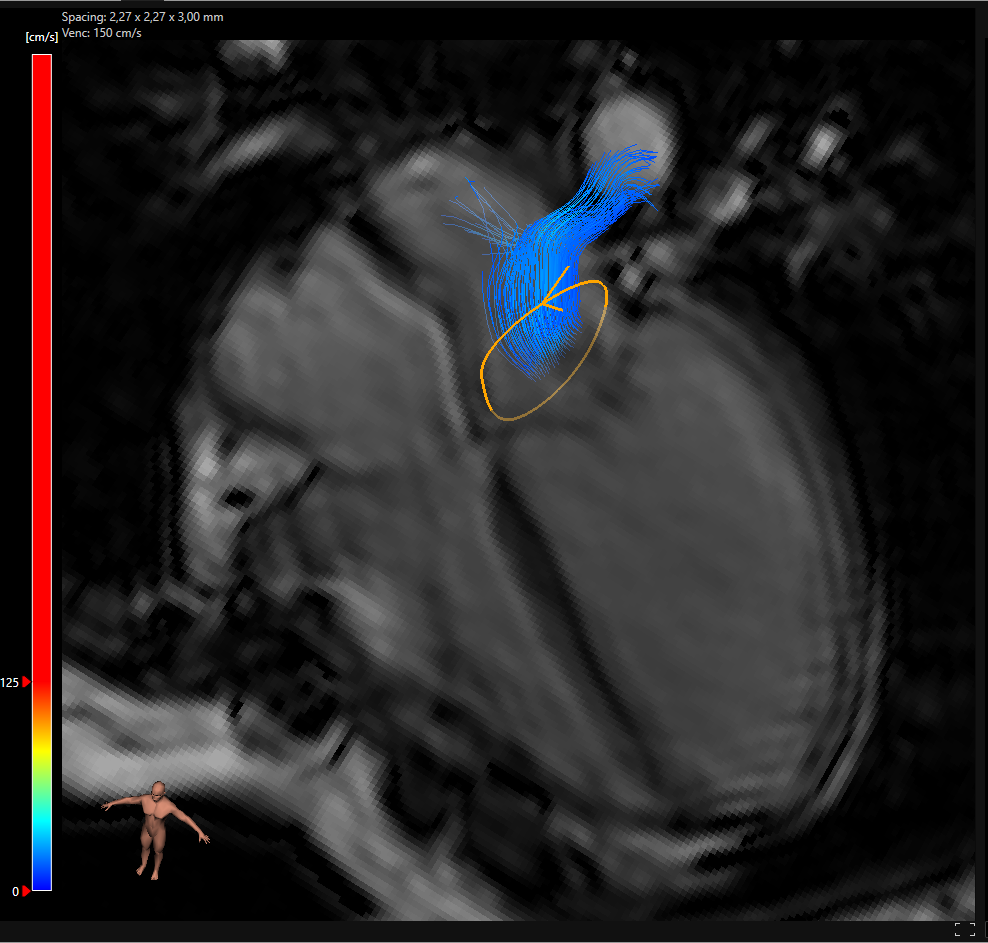

4D Flow MRI in Functional Assessment

When TTE and TEE findings are inconclusive or complex, 4D flow MRI plays a critical role. This technique captures time-resolved, three-dimensional data that maps the path and volume of blood through the mitral orifice.

It’s particularly useful in cases of:

• Moderate to severe mitral regurgitation

• Concomitant pulmonary hypertension

• Mitral valve regurgitation and mitral valve prolapse overlap

• Situations where mild mitral valve regurgitation and exercise cause symptoms

Our MR 4D Flow solution provides objective flow quantification, assisting in the staging of disease and tracking changes over time.